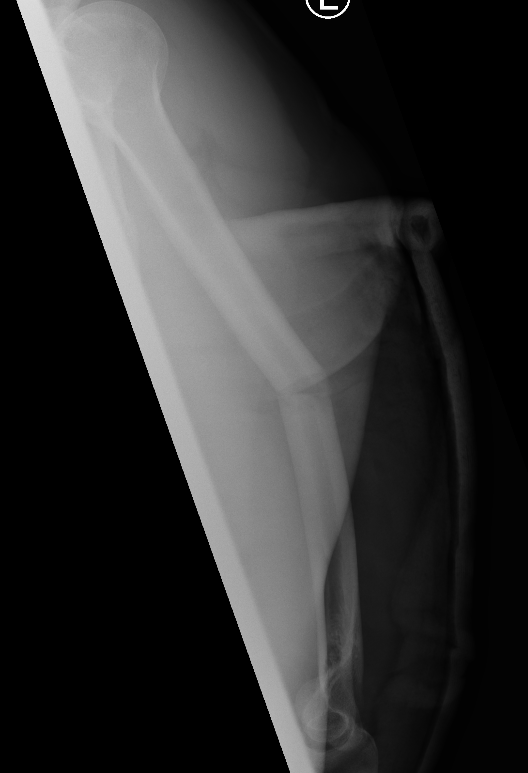

Displaced Humeral Fracture APDisplaced Humeral Fracture Lateral

Humeral Fracture SegmentalHumeral Plate LateralHumeral Plate Long AP

Segmental fracture ORIF